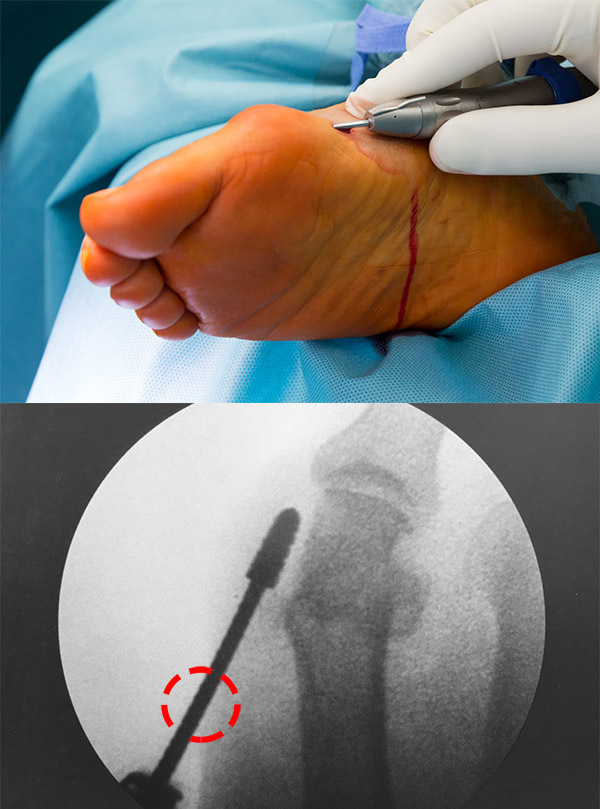

• Die Wahl der Inzisionen ist von entscheidender Wichtigkeit. Liegt der Zugang an einer falschen Stelle, wird die Zielstruktur nicht, bzw. nur in einem ungünstigen Winkel erreicht. Zusätzlich erhöht das Zerren an der Haut das Risiko für Wundheilungs­störungen. Für verschiedene Eingriffe gibt es klar definierte Zugangswege, die der Operateur kennen muss.

• Die Hautinzisionen befinden sich in ausreichendem Abstand vom zu adressierenden OP-Gebiet, so dass die Fräse auf ganzer Länge subkutan geführt wird. Andernfalls kommt es zu Läsionen der Inzisionsränder durch die Fräse.

• Die definierten Inzisionen berücksichtigen Hautspaltlinien, Blut- und Lymphgefäße, Nerven, Muskeln und Sehnen. Exponierte Punkte, an denen Schuhkonflikte mit den Narben auftreten könnten, sind zu meiden.

• Die Inzision ist klein, in der Regel zwischen 0,5 und 1 cm. Noch kleinere Schnitte erhöhen das Risiko für Wundheilungsstörungen und erschweren das Ausspülen des Bohrmehls.